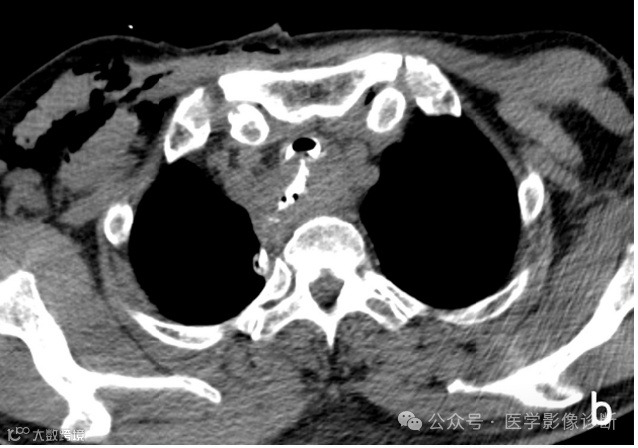

患者,男性,67岁,食管癌术后。

轴位 CT 显示食管癌术后变化(a, b)。然而,由于临床提供的申请表没有提醒,放射科医生只描述了术后变化,没有提及气管食管瘘。多平面成像(MPR)可以更好地显示瘘管。根据口服造影剂的使用情况,放射科医生应该明白医生想要观察是否发生了瘘管。